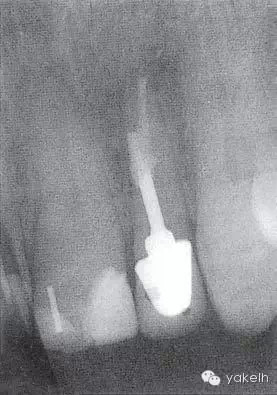

¤¤口外檢查可見顳下頜關(guān)節(jié)處輕微捻發(fā)音,開口度、開口型正常,無疼痛,未見其他異常??趦?nèi)檢查可見牙列中有部分良好的修復(fù)體,無齲壞;局部牙齦炎,探診出血,牙周探診深度不超過2mm。22唇側(cè)牙槽黏膜可見竇道(圖5.4.1a),輕微叩痛,竇道區(qū)捫痛,根尖X線片顯示牙根中部透射影,疑為樁穿孔(圖5.4.1b)。左上頜中切牙(21)和左上頜尖牙(23)對EPT和冷測試反應(yīng)正常。

圖 5.4.1(b)22根尖X線片,顯示樁穿孔側(cè)方的根周透射影。